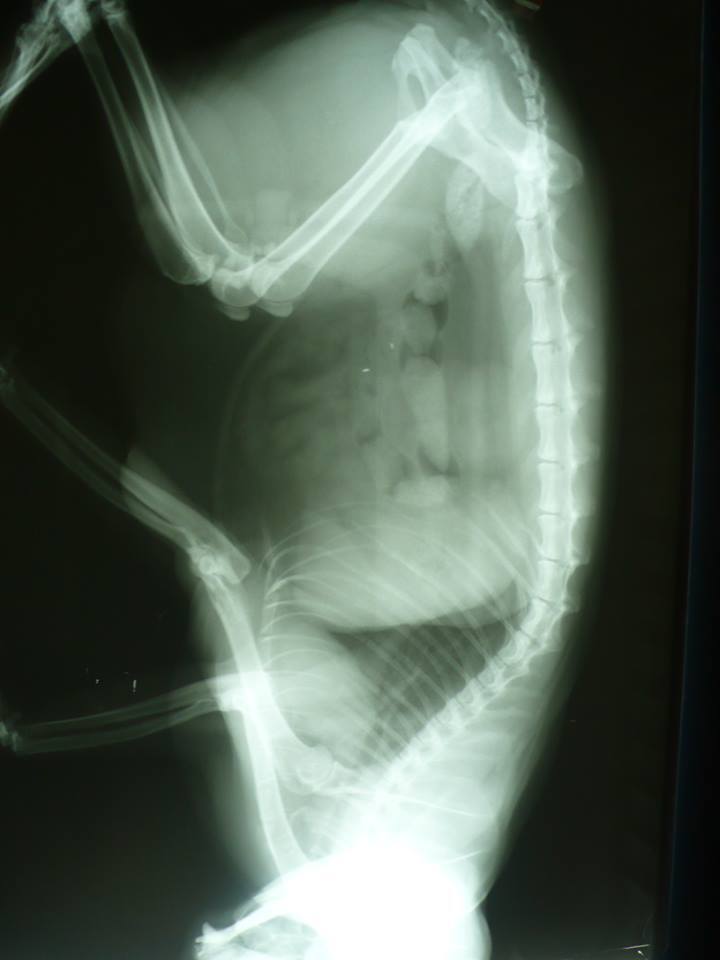

主題: 被車碾過骨盆斷裂 申請者姓名: 陳曉霏 花色: 申請日期: 2013-08-23 07:05:09 申請者部落格: 申請者臉書網址: http://www.facebook.com/xiaofeic 所在縣市/合作醫院: 台北市/極光動物醫院 治療費用: 27045元 需求人數: 29人 已結案 (2013-09-19 17:55:36) 報名人員: Cathy.H(已付款)、Yuri Chang(已付款)、grace0710(已付款)、Lilo Hsueh(已付款)、虎咪(已付款)、沈明明(已付款)、peggy(已付款)、Nancy Chiou(已付款)、FiFi(已付款)、Ekim Lu(已付款)、陳曉霏(已付款)、李昭慧(已付款)、Annisui Strauss(已付款)、王千枝(已付款)、周 昊暵(已付款)、哇咧蹦 x14(已付款)、 候補人員: 動物病情說明: 路上看到一隻貓躺著不能動

請醫生檢查後 骨盆的地方有斷

疑似躺在車下睡覺 被壓過去

前腹側還有一個滿大的疝氣

才會整個被碾過去動物近況說明: 目前骨盆處骨頭還在修復中